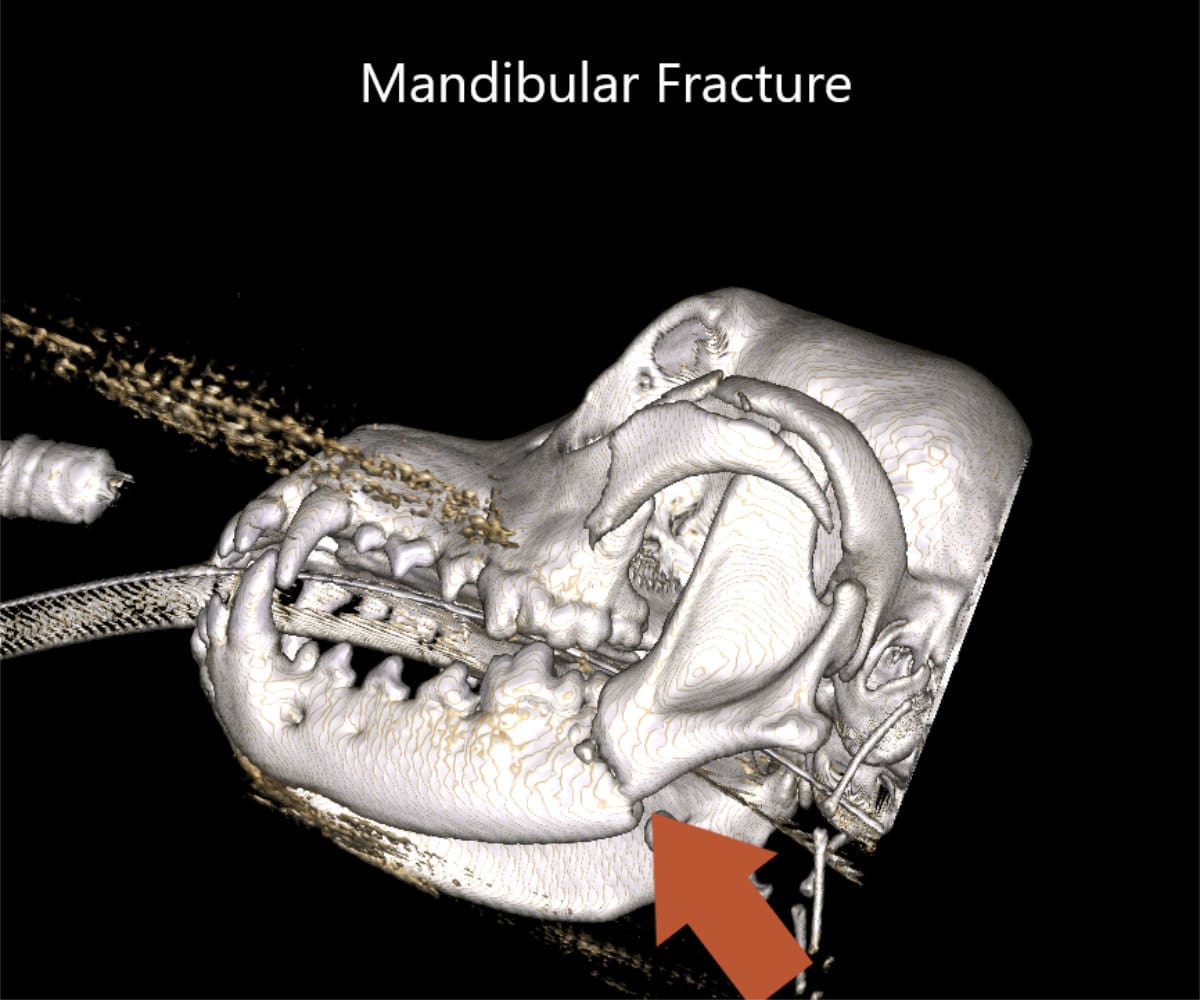

The advantages extend beyond diagnosis, as CBCT enables intricate 3D reconstructions of the skull, providing invaluable support to our doctors in the meticulous planning process for facial plating procedures.

Our CBCT VetCAT unit is easily rolled up to our treatment table and takes only 40 seconds to complete a scan. It has proven to be invaluable in the diagnosis and treatment planning for pets with periodontal, endodontic and cancerous disease conditions. It is also indispensable in the evaluating our trauma cases with jaw fractures.